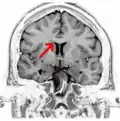

![]() Corpus callosum from above, front part at the top of the image | |

Coronal T2 (grey scale inverted) MRI of the brain at the level of the caudate nuclei emphasizing corpus callosum -